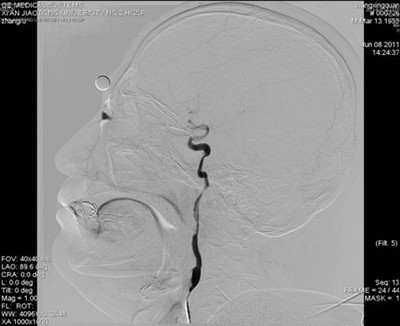

图2 侧位片:左侧颈内动脉血管内可见混杂密度团块影,且重度狭窄

患者送入我院时意识模糊,右侧肢体完全不能移动,不能言语,我院神经内科按照脑梗死应急预案,通过急性脑梗死绿色通道立即行头颅CT排除脑出血。考虑脑梗死,但病灶尚未显示,有急诊动脉介入治疗的指证和时间。吴海琴主任和张桂莲副主任立即向家属谈病情并介绍介入治疗的利弊,同时展淑琴副主任医师和卜宁及孙宏主治医师指导完成术前各项准备工作并加用基础治疗。家属了解病情后签字同意介入治疗。吴海琴主任、张桂莲副主任、张茹副主任医师立即在祁小江技师、赵菊凤护士的配合下给患者行脑血管造影,造影见左侧颈内动脉内有异常混杂密度团块影,并局部重度狭窄,远端血管血供极差,考虑血栓形成所致狭窄。虑及动脉溶栓有可能使血栓脱落,栓塞远端血管,遂在保护伞的保护下给局部狭窄部位安放2枚支架,把血栓压住贴壁,使狭窄的颈内动脉基本恢复正常,远端血供恢复,患者意识清楚,右侧肢体能够在床头移动。此时距离患者发病仅4小时。今晨患者右侧肢体能够抬离床面并对抗阻力,能连续说出数个单词。